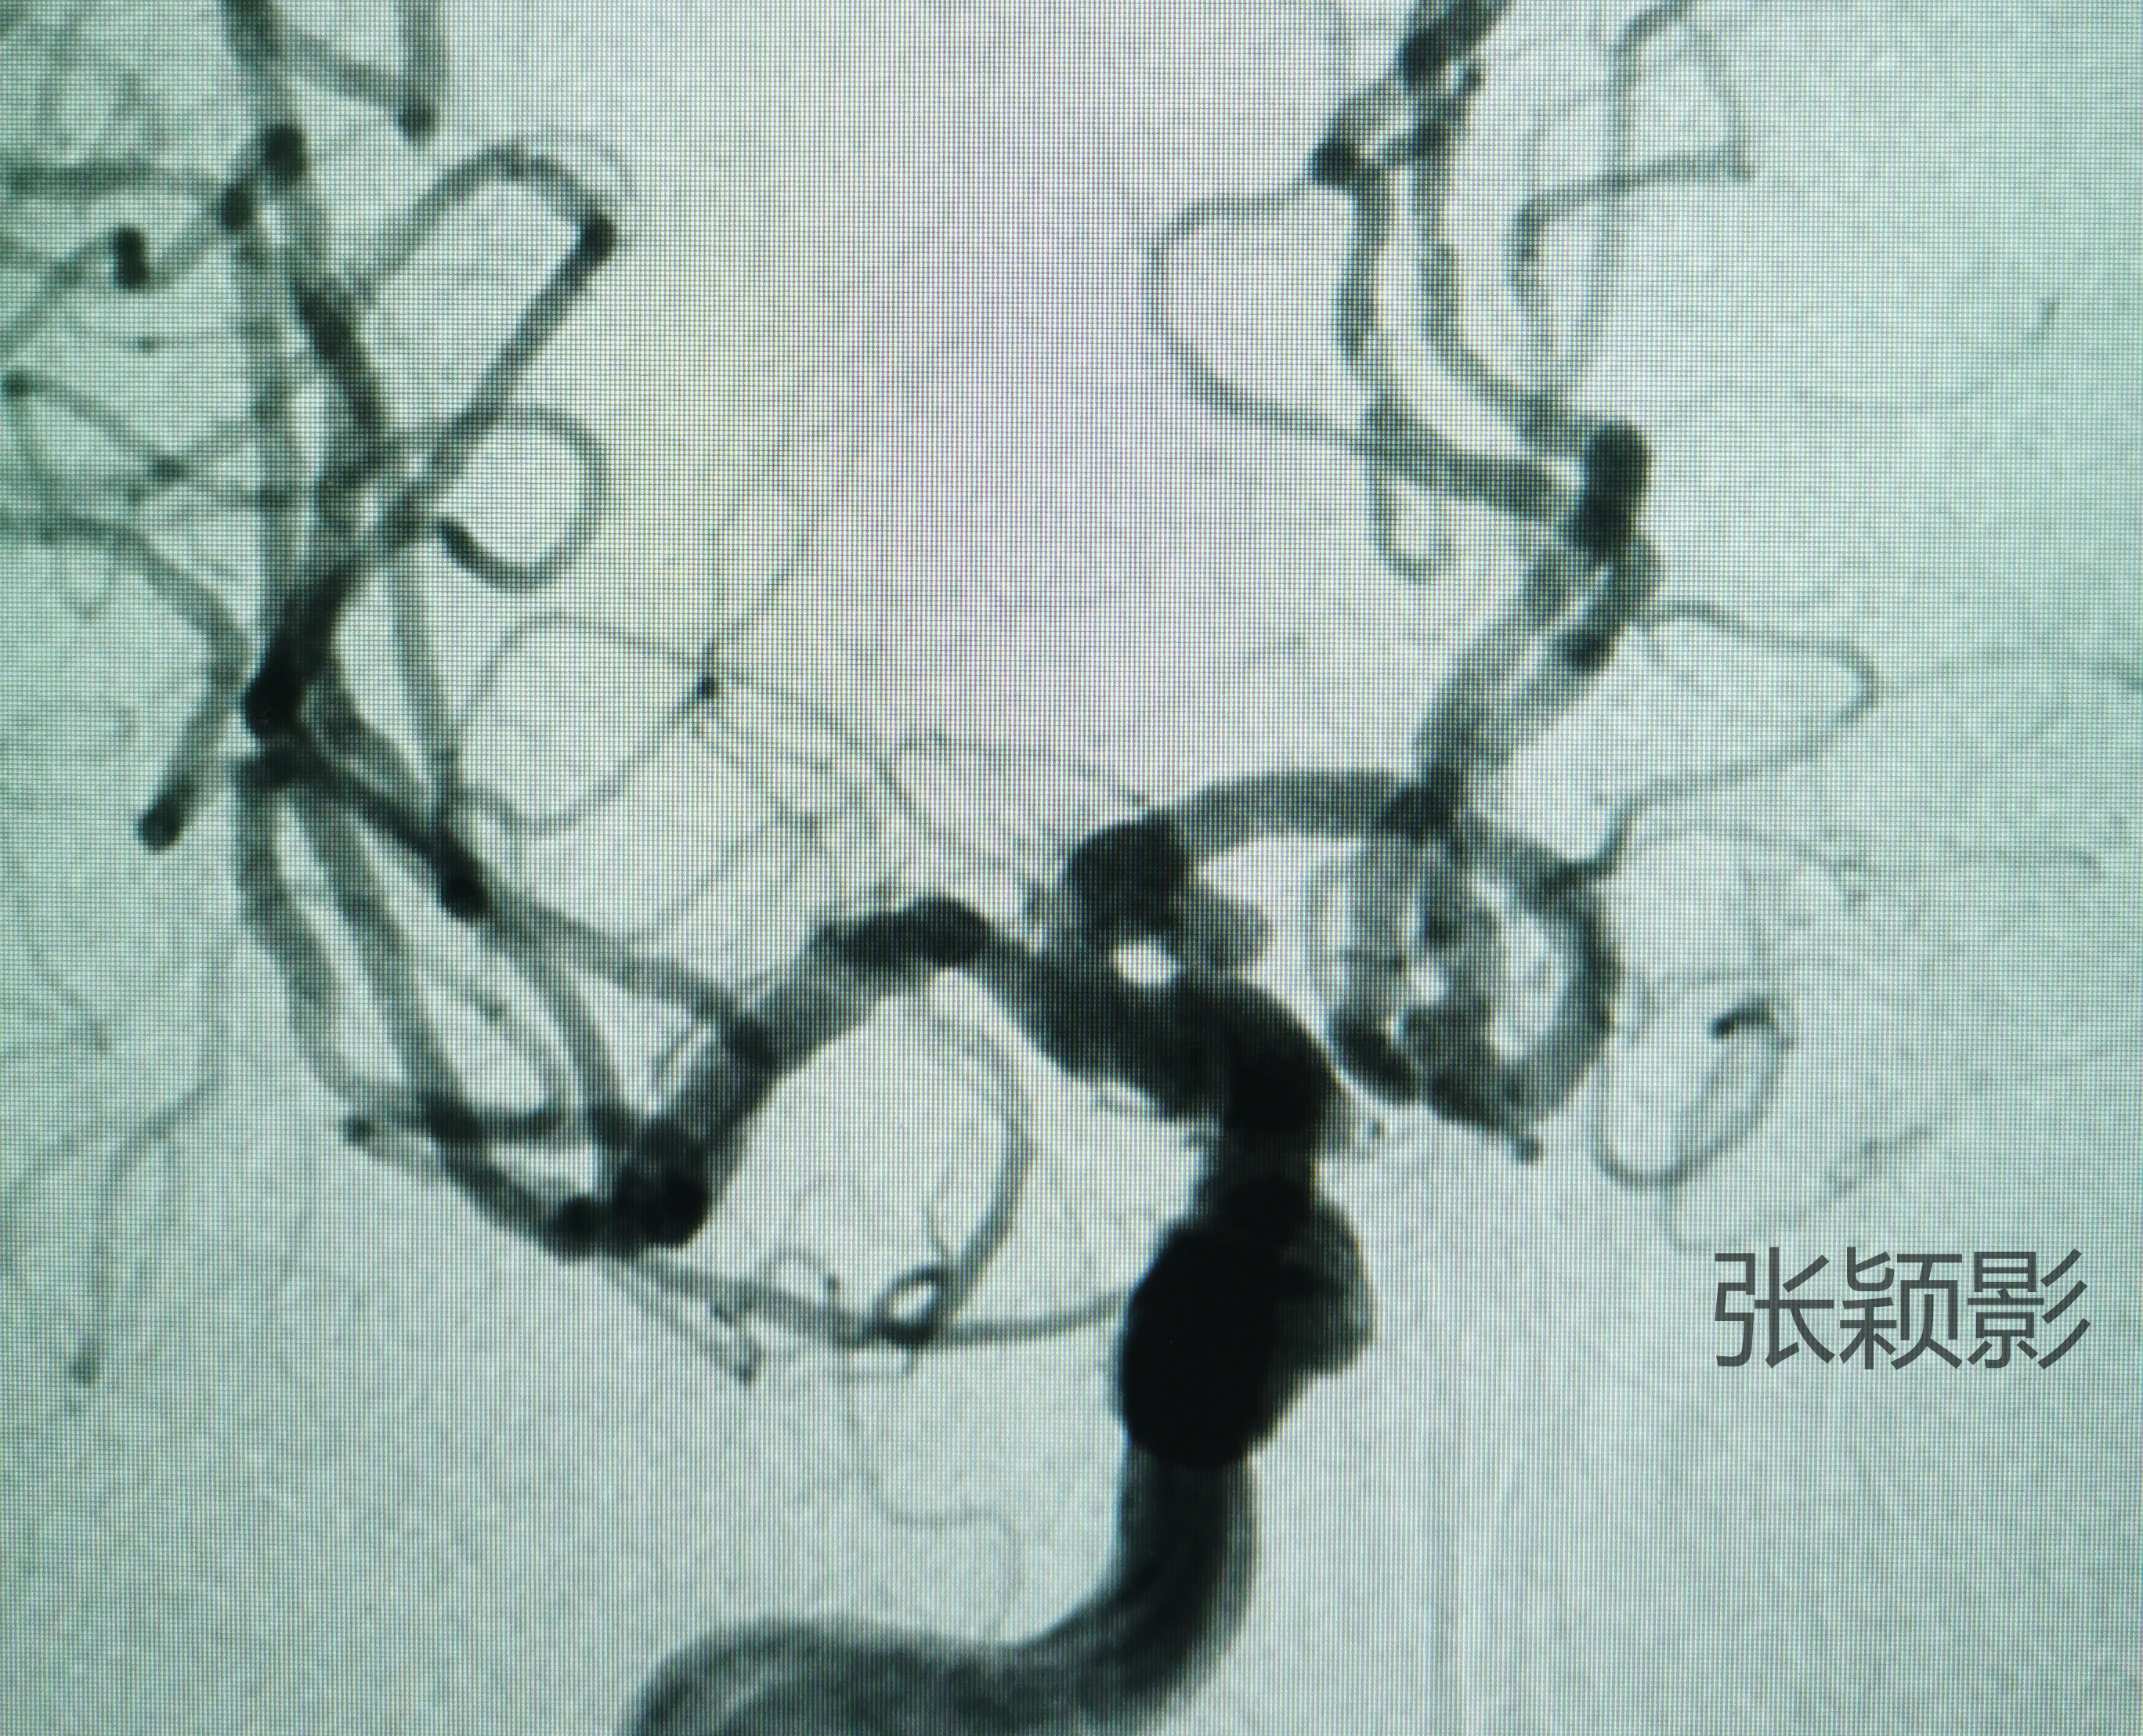

侧位造影提示瘤体指向后下,动脉瘤外形不规则,可见凸起子囊,存在破裂风险。

通过旋转影像可以看到,栓塞路径略扭曲,动脉瘤-载瘤动脉-近段血管连续成角。近段颅内颈内动脉存在硬化狭窄,中间导管到位于此,必须避免对于斑块的刺激,若导致术中血栓事件,则对于未破裂动脉瘤患者而言得不偿失。